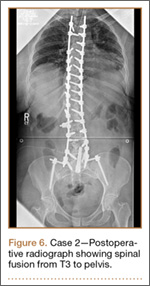

Development and Diagnosis of PRES. The patient made significant progress with physical therapy and developed episodes of hypertension at night on postoperative days 4 to 6. Her mean peak systolic blood pressure was 180 mm Hg. This improved after oral beta-blocker therapy. On postoperative day 6, the patient was ambulating with physical therapy and the aid of a walker. She was found to be neurologically intact, was resting comfortable in a chair reading a book, and was cleared for transfer to a rehabilitation facility the next day. During the morning on postoperative day 7, she developed confusion and visual loss. The patient reported blurry vision followed by complete bilateral painless loss of vision aside from mild light perception. She was unable to identify any objects. She had extinction to double simultaneous stimuli and evidence of agraphesthesia in the left hand. Her neurologic examination was otherwise at baseline. Upon emergent imaging, head CT showed bilateral symmetric areas of hypodensity involving the cortical and subcortical white matter of both occipital lobes (Figure 3). MRI showed extensive bilateral cortical and subcortical signal hyperintensity involving the parietal and occipital lobes (Figure 4). No evidence of petechial or lobar hemorrhage was found.